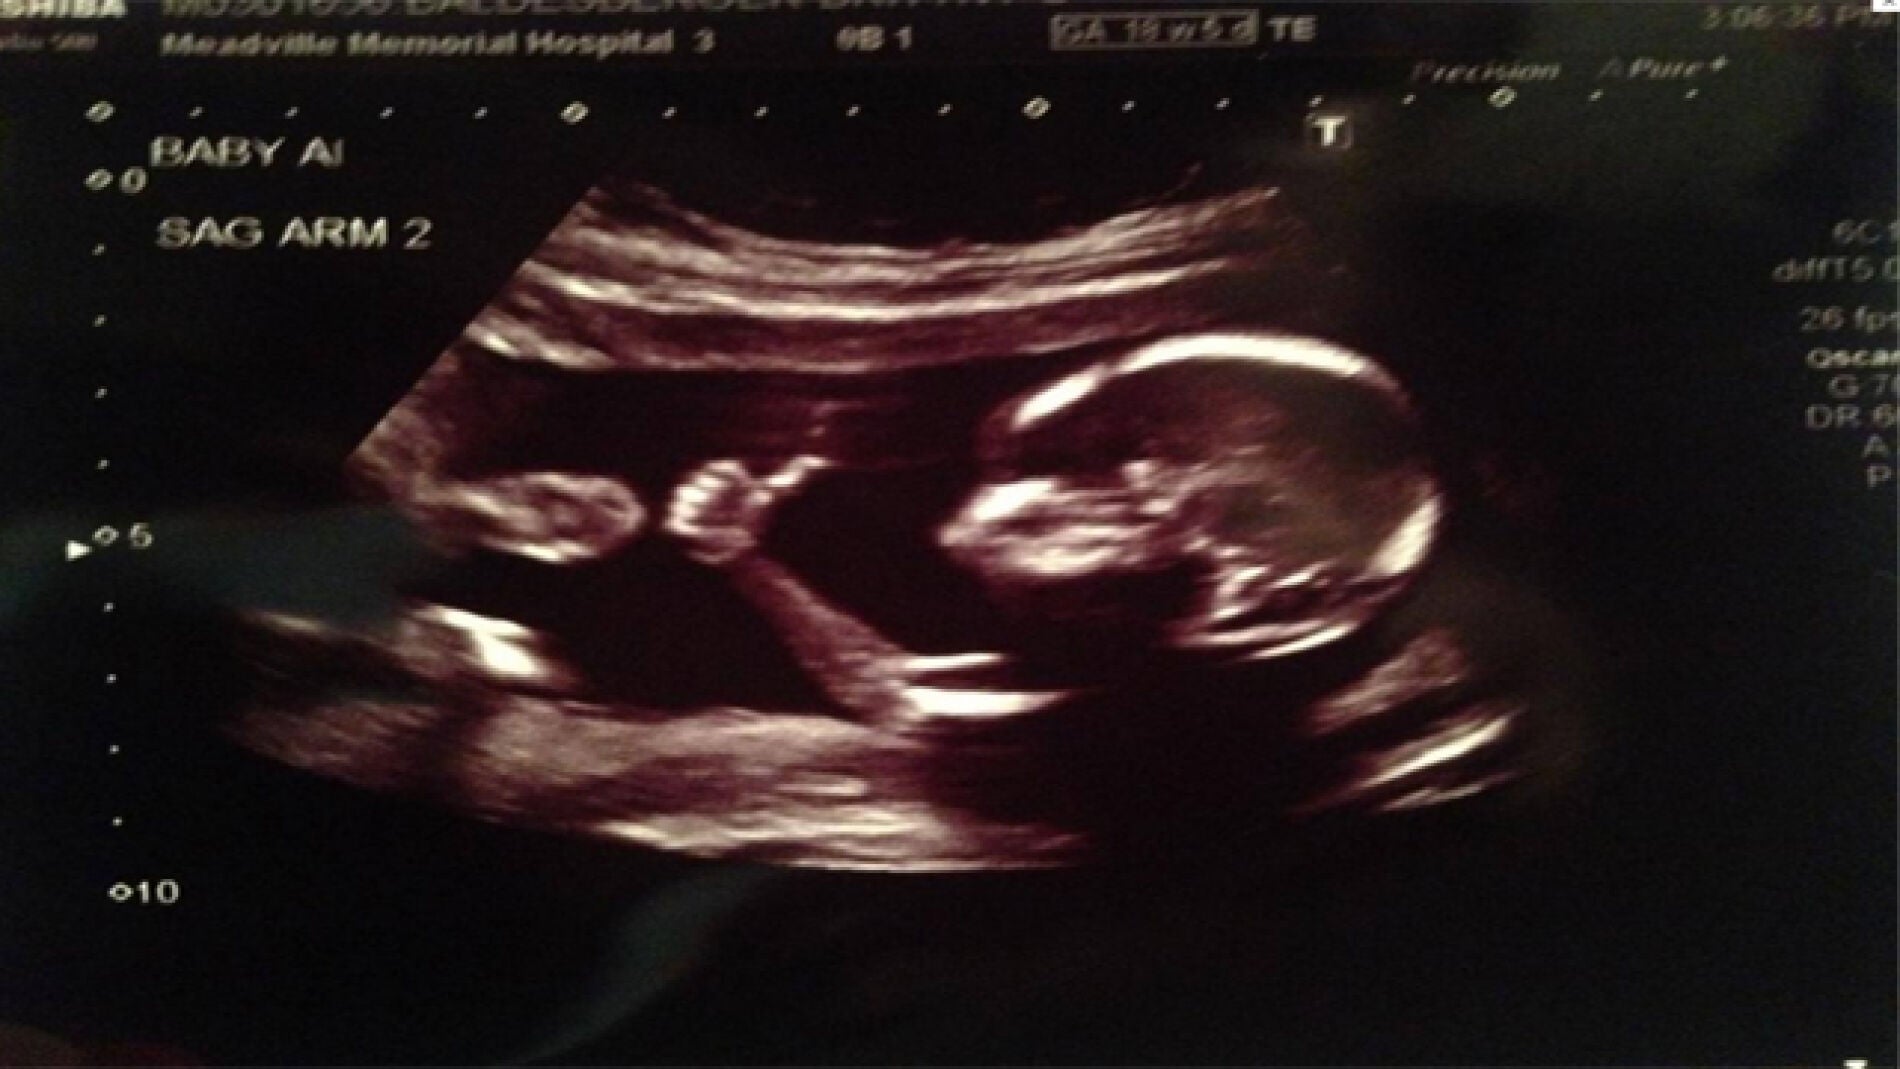

Un feto de 18 semanas levanta el pulgar haciendo el gesto de OK

En una ecografía rutinaria y con sólo 18 semanas un feto levantó el pulgar con la expresión de 'todo va bien' ante el asombro de sus padres. Hasta el momento más de dos millones de internautas han visto la imagen en el perfil de 'Reddit' del progenitor en solo 24 horas.

Solemos entender el gesto de un pulgar hacia como la expresión de que 'todo va bien'. Con tan sólo 18 semanas un bebé realizó este gesto ante sus papás en una ecografía según publica el diario 'The Independent'.

Ante este gesto, poco habitual para un feto, el padre de la criatura colgó la imagen en su perfil de la red social 'Reddit', donde más de 2 millones de personas ya han visto la imagen. La sorpresa de los internautas fue mayor cuando descubrieron que estos padres estaban esperando gemelos, muchos se preguntaron si el otro bebé estaba de acuerdo con el gesto de su hermano viendo la cómoda postura en la que se encontraba el primero.